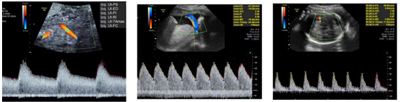

Gestante, 35 anos, primigesta, com 33 semanas de gestação, calculado pela ultrassonografia precoce, vem a consulta de pré-natal sem queixas. Ao exame físico apresenta PA 110 x 70 mmHg, altura uterina de 29 cm, BCF 140 bpm, dinâmica uterina ausente. Paciente traz ultrassom realizado com 32 semanas com peso estimado de 1350g (< percentil 3), ILA 7,8 cm, Doppler da artéria uterina, cerebral média e umbilical conforme imagem a seguir:

Indique o diagnóstico e conduta corretos.